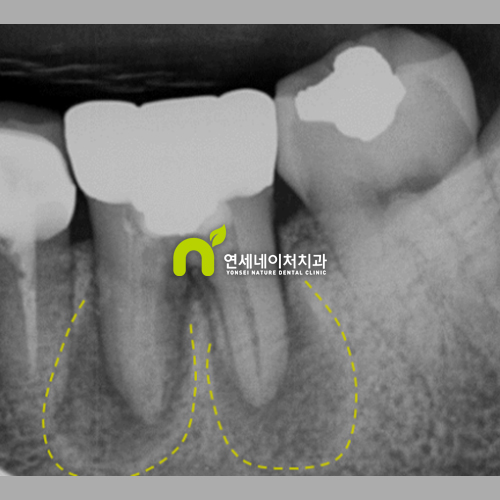

뿌리 끝 염증 생겼을 때, 발치하지 않고 재신경치료를 통해 해결하기

뿌리 끝 염증 생겼을 때, 발치하지 않고 재신경치료를 통해 해결하기 안녕하세요. 자연치아를 살리는 연세...